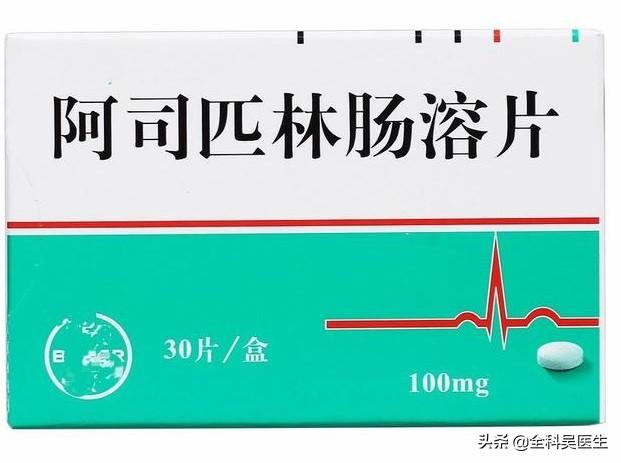

最後に、心臓ステントを留めた後に注意しなければならないこと。ステント留置術の安全性を心配するよりも、患者さんが術後に注意することが重要です。ステント留置術は万能ではなく、永久的なものでもないことを知っておくことが重要である。ステント留置後、患者の心機能はすでに影響を受けており、ステント留置は重度に閉塞した血管を取り除く対症療法に過ぎない。既往の危険因子は常に存在し、血管が再び閉塞する危険性はまだある。したがって、ステント留置後も、アスピリンやクロピドグレルなどの抗血小板凝集薬、リジュベネート・ロスバスタチン・カルシウム錠などのスタチン系薬剤、シンカン一硝酸イソソルビド錠などの硝酸塩系薬剤は長期間服用しなければならないので、特に注意が必要である。生活習慣としては、アルコールとタバコを控え、軽い食事、適度な運動、規則正しい仕事と休養、仕事と休養の両立、落ち着いた心の維持、健康的な体重の維持が大切です。また、定期的な見直しにも気を配るようにしましょう。

- 1.抗血小板凝集薬:血小板凝集は局所血栓症の重要なプロセスであり、血小板凝集を予防することで血栓症を予防し、狭窄や閉塞の再発を防ぐことができる。一般に狭窄はステント留置後6ヵ月以内に起こりやすいので、特別な禁忌がなければ狭窄を予防することができる。通常、術後1年間は二重抗血小板薬(アスピリン+クロピドグレル)が必要である。。2種類の抗体を1年間使用した後は、何もなければ1種類の抗体による予防(通常はアスピリンが望ましい)を生涯続けるべきである。

心臓へのステント留置は確かに大きな病気である。治療前の血管造影も治療後のステント留置も緊急措置である。血管造影の過程で、血管が深刻に閉塞していることが判明し、それはすでに冠動脈性心臓疾患であるため、緊急援助を使って狭窄した血管を拡張し、比較的滑らかな流路を開くことが合理的である。ステントを留置した後も、閉塞の原因となっている元の病原体は除去されていないため、ステント留置部の水路を維持するために費用と時間を費やさなければならない。アスピリン腸溶錠、タジン錠、ポラリス錠、高血圧、高血糖、たくさんの薬を1年以上服用しなければならない。病気のために薬を飲み、病気を克服し、生活のために薬を長期間服用することは、現代の高齢者の一般的な生き方である。この長い自宅での生活、出血を防ぐ閉塞予防、自分の槍で相手を攻撃する、戦国時代の寓話の解釈。金属で汚れた血と肉の心によって、私はステントリアンとして、少し生々しいようだ。少し病的だが、大きな病気ではなく、確かに祝うべきことだ。